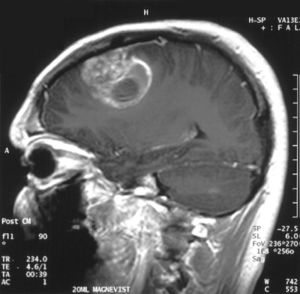

| تصوير بالرنين المغناطيسي للمنطقة التاجية يظهر الورم الأرومي الدبقي في ذكر في الخامسة عشر من عمره. | |

- اختبارات التصوير: وغالبًا ما يستخدم التصوير بالرنين المغناطيسي للمساعدة في تشخيص أورام الدماغ. في بعض الحالات، قد يتم حقن صبغة (مواد تباين) خلال وريد في ذراع المريض أثناء دراسة التصوير بالرنين المغناطيسي للمساعدة في إظهار الاختلافات في أنسجة الدماغ.

قد يساعد عدد من مكونات التصوير بالرنين المغناطيسي المتخصصة — بما في ذلك التصوير بالرنين المغناطيسي الوظيفي، وتصوير التروية بالرنين المغناطيسي وتنظير الطيف بالرنين المغناطيسي — في تقييم الطبيب للورم وخطة العلاج.